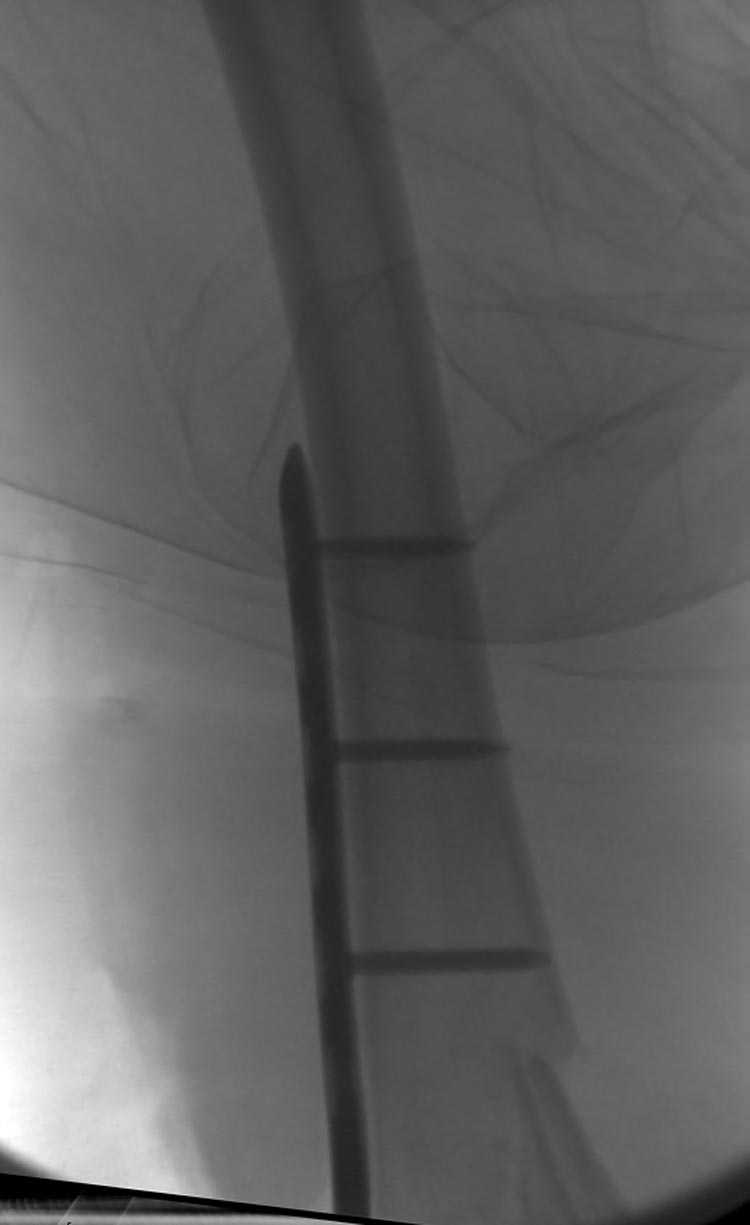

Бесспорно, предлагаемый ретроградный метод имеет свои преимущества, но имеется опасность при манипуляции интрамедуллярным гвоздем расколоть мыщелки.

Раскол можно предупредить шурупами, но короткий дистальный фрагмент навряд ли позволит добиться адекватной стабильности конструкции. Стандартные гвозди не рассчитаны для таких переломов, и если все таки желаете провести фиксацию гвоздем, тогда надо заказывать специальный custom made nail т.е. с расширенной возможностью дистальной блокировки.

Поэтому такие меж и над- мыщелковые переломы более предпочтительным считается фиксировать мыщелковыми пластинами

Устанавливается из малого разреза "не вскрывая сустав" со стороны латерального мыщелка, и Insertion Jig позволяет установить пластину "мостовидно" перкутанно в проксимальном отделе, "не вскрывая и не трогая" место перелома.